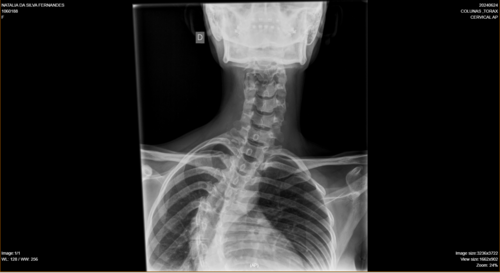

Olá, me chamo Natália da Silva Fernandes, tenho 21 anos, moro na cidade de Ji-Paraná, no estado de Rondônia. Fui diagnosticada com escoliose e venho na busca de um tratamento pelo SUS há um tempo, mas não obtive retorno até o presente momento. Passei por algumas consultas com ortopedistas do SUS, peguei encaminhamentos para passar com um neorocirurgiao e depois de um longo período de espera, consegui uma consulta com um neorocirurgiao do SUS, quando ele viu meu estado de saúde ele disse q a única solução é fazer a cirurgia, como na cidade não tem estrutura para realizar a cirurgia através do SUS, peguei mais um encaminhamento para consultar pela segunda vez por outro neurocirugiao, mas na cidade de Porto Velho, e nisso fiquei no aguardo desse agendamento mas até o momento nenhum retorno do SUS, ou seja, nenhum pedido de agendamento de cirurgia, apenas consultas, é um processo burocrático conseguir uma cirurgia pelo SUS, pois tem uma lista de pacientes na espera por vaga. Devido à demora do SUS , recorri a um neurocirurgião particular e o diagnóstico que recebi foi o mesmo, necessito fazer a cirurgia com urgência.Atualmente, me encontro num quadro doloroso, minha escoliose está com 86° de encurvatura, sinto dores constantes, tenho dificuldade em andar e às vezes dificuldade em respirar, porque são dores muito fortes. Para dormir, é uma luta constante para achar uma posição que dê menos desconforto . Diante de todo esse processo doloroso, e todo o tempo que venho recorrendo ao SUS e não obtendo uma solução favorável, a preocupação aumenta cada dia, pois não tenho condições de custear nem a cirurgia, nem o tratamento pós-cirúrgico. Foi então que surgiu a solução de fazer a vaquinha. A cirurgia fica em média de 250 mil reais com o tratamento pós-cirúrgico. Deixo na descrição os laudos e exames que venho realizando como transparência da minha situação.Toda ajuda é bem-vinda!Ajude-me compartilhando em suas redes sociais. Deixarei minha rede social para entrarem em contato comigo para mais informações: @_fe3_n47ou acesse o link abaixo e vá direto ao meu perfil.https://www.instagram.com/_fe3_n47?igsh=MXA1bDEzNW53YzZ5NA==